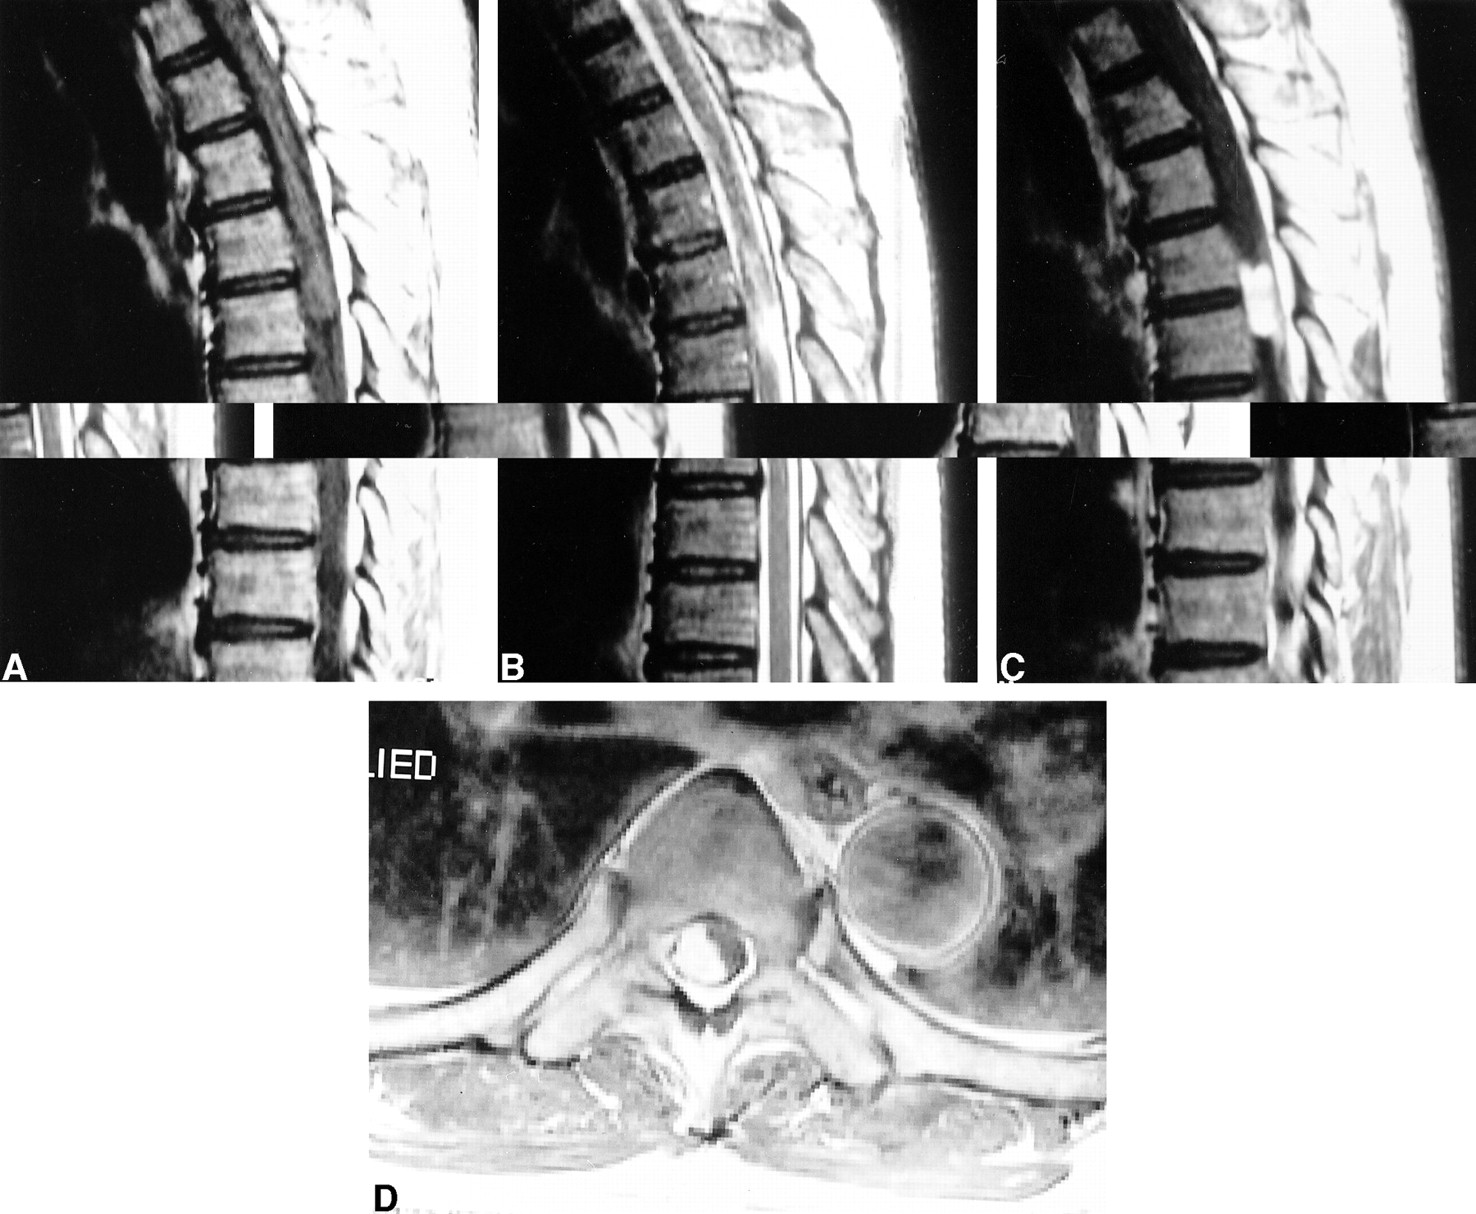

Case 1 (Figure 1)

Case 1.

Sagittal T1-weighted (A), T2-weighted (B), and contrast-enhanced T1-weighted (C) MR images show a well-defined solid enhancing mass within the thecal sac at the L1 level. A vertical linear enhancing structure within the thecal sac, as seen on C, is presumably due to a radiculomedullary vein rather than a compressed root with breakdown of nerve-blood barrier. On a photomicrograph of capillary hemangioma (D), the excised tumor consists of lobules of small capillary-sized vessels (C) separated by fibrous septa (S). Note a feeding vessel (F) with larger caliber size and medium-sized branching vessels (B) (H&E, ×40).

A 28-year-old man presented with left gluteal and back pain developed 1 month prior to admission. On physical examination, motor strength of both lower extremities was decreased, in association with paresthesia. Straight leg raising of the left lower extremity was 60°, and that of right lower extremity was 90°.

MR imaging of the thoracolumbar spine showed a well-circumscribed intradural mass at the L1 level. This mass was located in the posterior portion of the dural sac, displacing the cauda equina anteriorly. The mass was isointense relative to the spinal cord on T1-weighted images and slightly hyperintense on T2-weighted images. On contrast-enhanced T1-weighted images, the tumor showed strong homogeneous enhancement. Preoperative diagnosis was either neurinoma or meningioma.

At surgery, a 1.5 × 1.0 × 1.0- cm3 bright pinkish smooth mass was found to be densely attached to the cauda equina with no dural attachment.

The tumor was totally removed. Histologically, the mass comprised a proliferation of capillary-sized vessels lined by flattened endothelial cells, and the mass was composed of nodules of small capillary-sized vessels supplied by a feeding vessel, indicating capillary hemangioma.